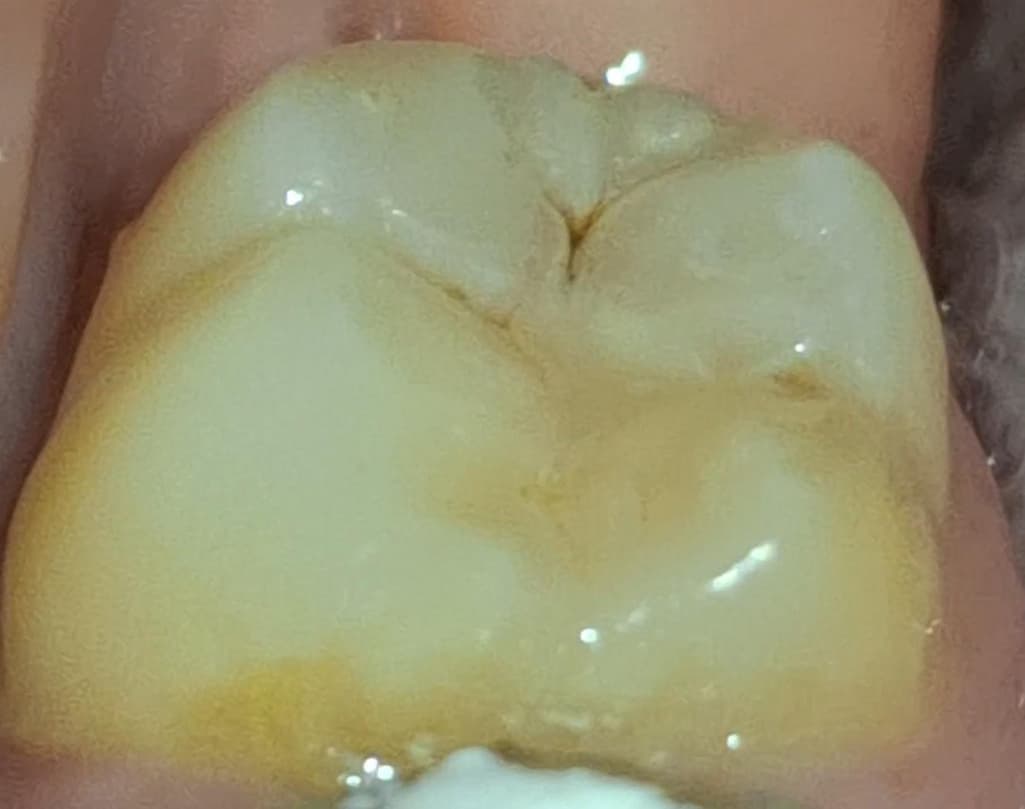

제가 궁금한 부분은 레진 벗겨진 곳에 갈색 자국이 있어도 되는건가요? 저것도 정지우식이라서 그냥 레진으로 덮으신걸까요?

사진에 상에 보이는 충치는 치료를 해야될것같으니 치과에 가셔서 검진후 치료를 받으시는게 좋을것같습니다.

사진으로 봤을 떄에는 정지우식같아 보이기는 합니다만 벗겨졌다면 재치료 받으시면 됩니다.

사진으로 봤을 경우에는 치아에 홈이 생긴 것으로 보입니다. 치아에 홈이 생기게 되면 대부의 이물질이 들어가게 되어 충치가 더 커질수 있습니다. 이런 경우 홈이 있는 부분을 메꿔주는 것이 좋을 수 있습니다.

빨간원 안쪽도 그렇고 그 옆쪽도 아직 충치가 있어보입니다 치과가서 해당 부위 전반적으로 다시 봐달라고하세요